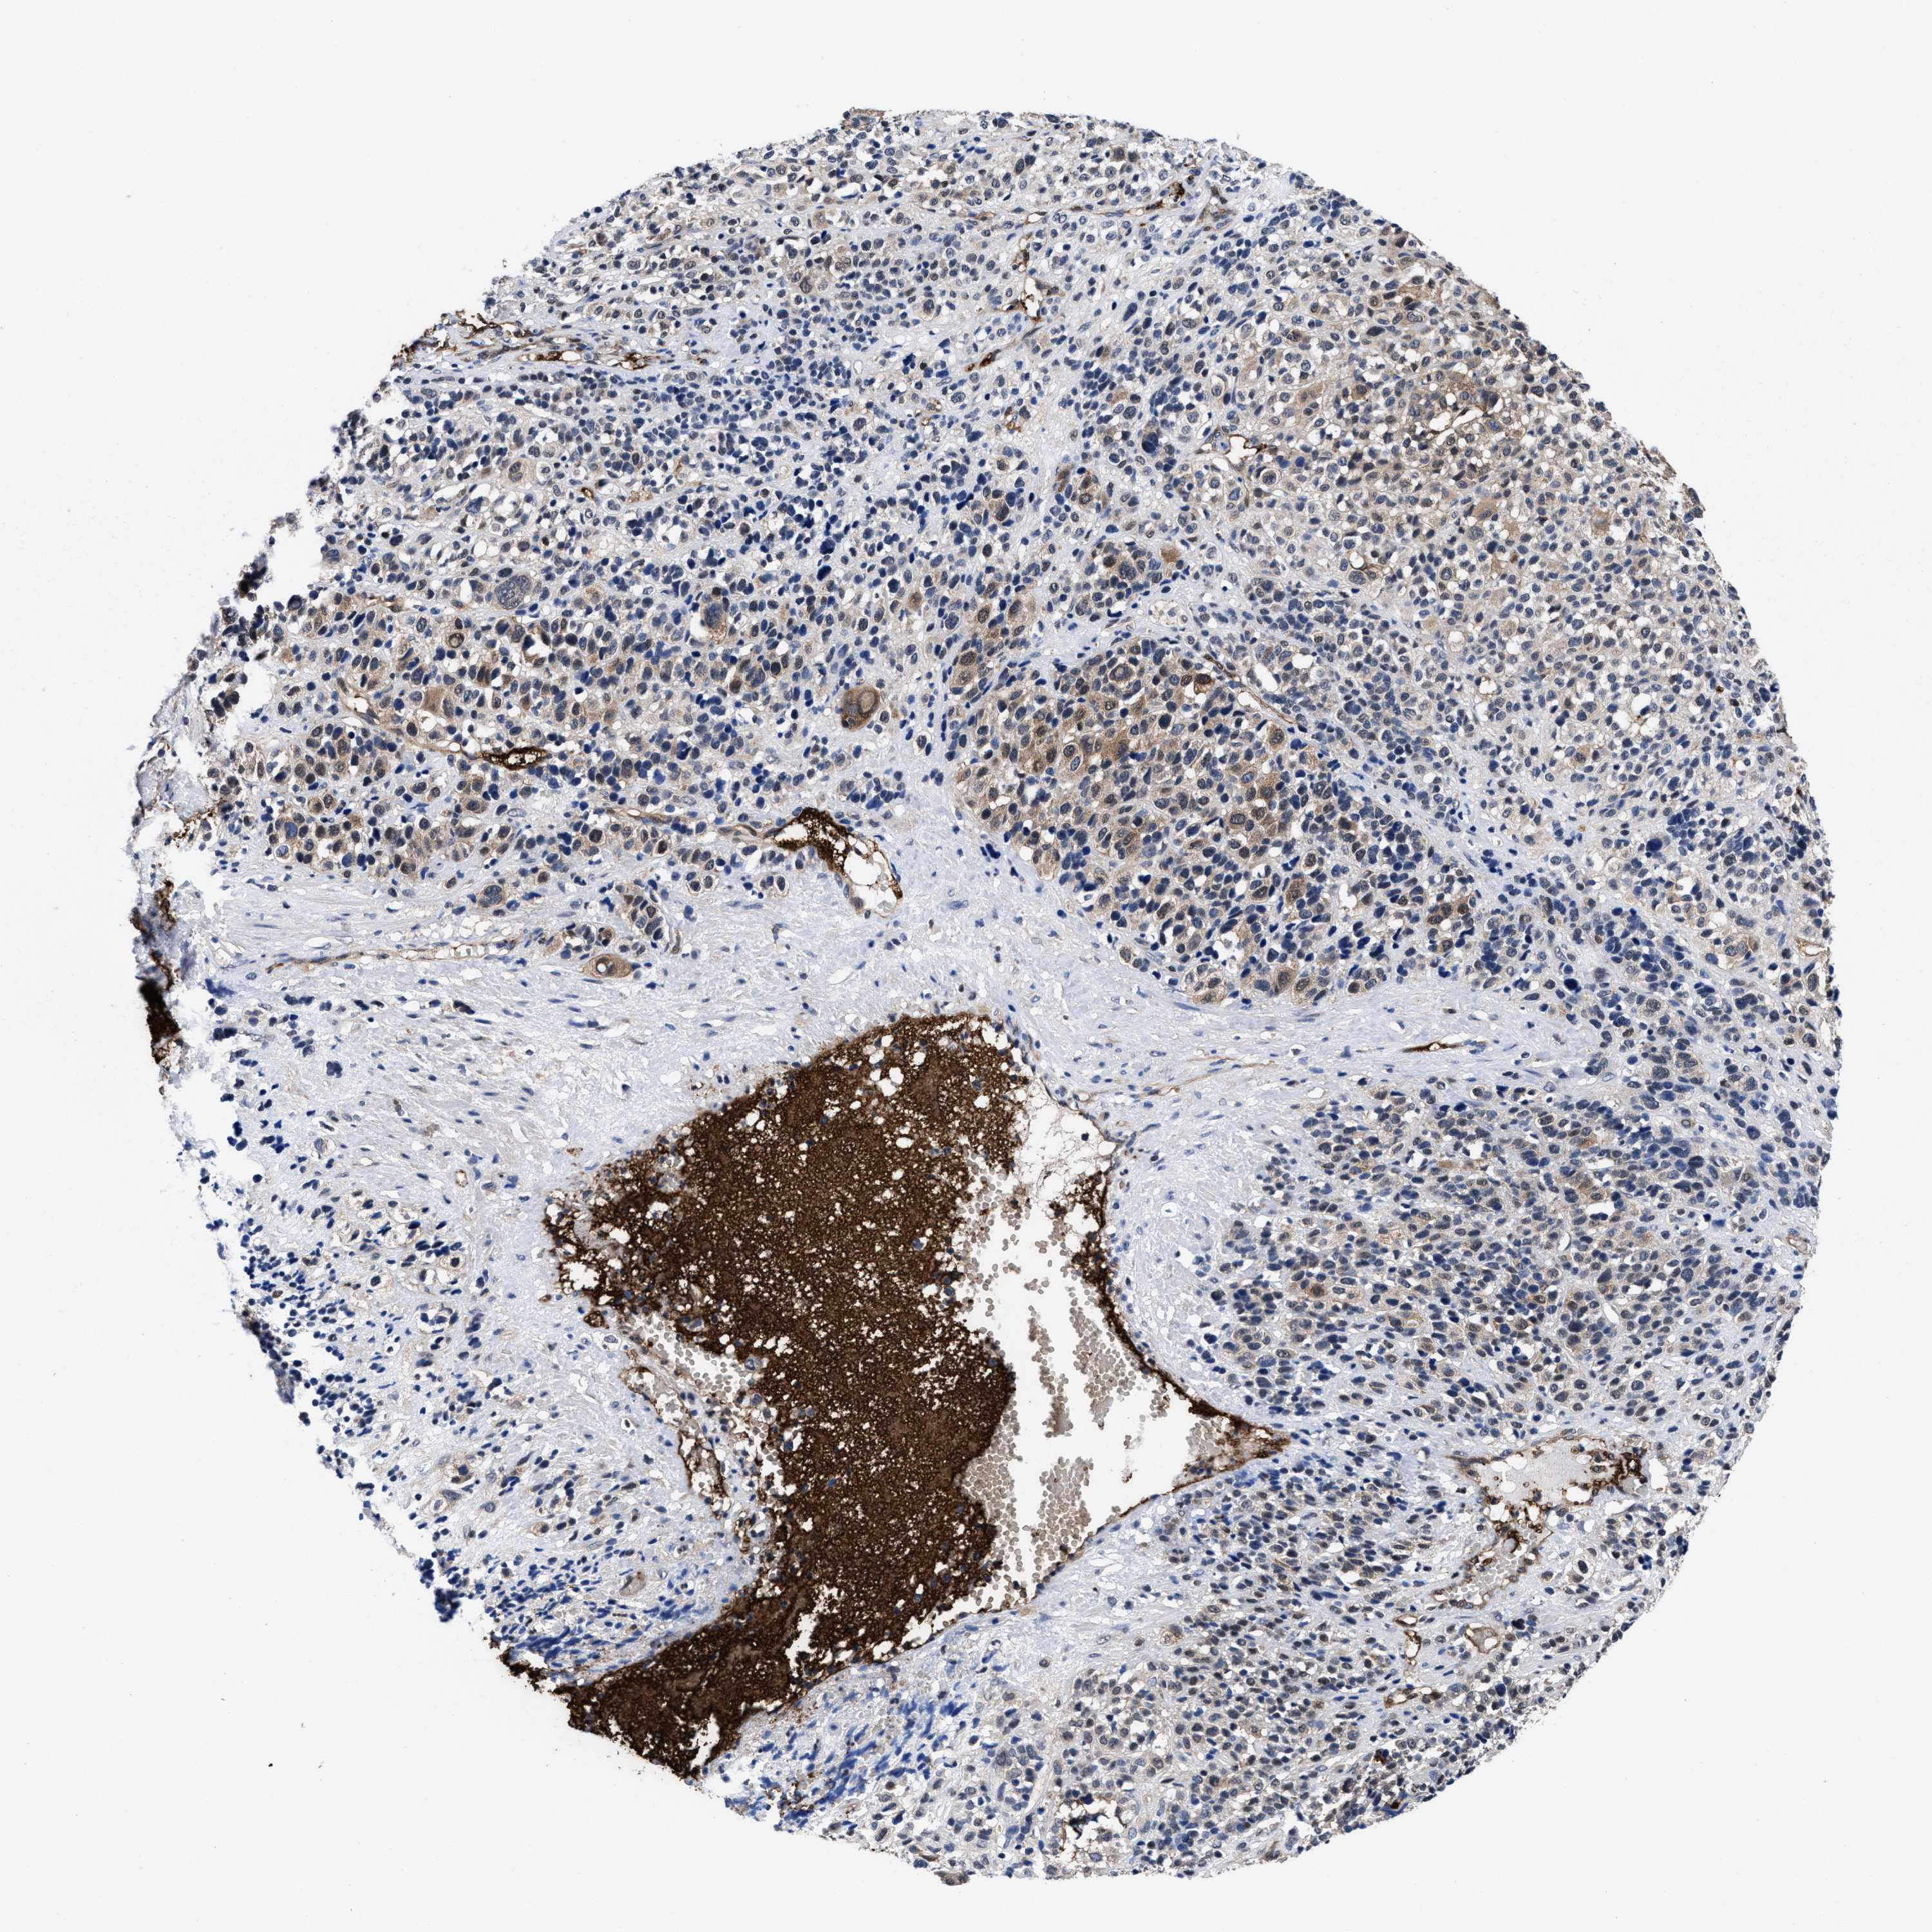

MELANOMA - Protein expressioni

A mouse-over function shows sample information and annotation data. Click on an image to view it in a full screen mode. Samples can be filtered based on level of antibody staining by selecting one or several of the following categories: high, medium, low and not detected. The assay and annotation is described here.

Note that samples used for immunohistochemistry by the Human Protein Atlas do not correspond to samples in the TCGA dataset.

Antibody stainingi

Antibody staining in the annotated cell types in the current human tissue is reported as not detected, low, medium, or high, based on conventional immunohistochemistry profiling in selected tissues. This score is based on the combination of the staining intensity and fraction of stained cells.

Each image is clickable and will lead to virtual microscopy that enables deeper exploration of all samples and also displays staining intensity scores, fraction scores and subcellular localization as well as patient and tissue information for each sample.

HPA022434

HPA022953

HPA022959

HPA028758

CAB007783

Staining

High

Medium

Low

Not detected

Intensity

Strong

Moderate

Weak

Negative

Quantity

>75%

75%-25%

<25%

None

Location

Nuclear

Cytoplasmic/membranous

Cytoplasmic/membranous,nuclear

Malignant melanoma, NOS

Malignant melanoma, Metastatic site